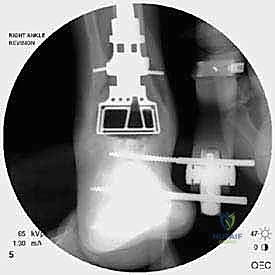

مراجعة مفصل الكاحل الصناعي هي إجراء جراحي ضروري لمعالجة المشاكل التي قد تنشأ بعد الجراحة الأولية، مثل كسور الكعبين أو عدم استقرار المفصل. يتضمن العلاج التشخيص الدقيق عبر الأشعة السينية والتصوير المقطعي، يليه التدخل الجراحي لتثبيت الكسور واستعادة وظيفة الكاحل، مع التركيز على التعافي المبكر.

تُعد جراحة مراجعة مفصل الكاحل الصناعي (Revision Total Ankle Replacement) من الإجراءات الجراحية المتقدمة والبالغة الدقة في عالم جراحة العظام الحديثة. لا تقتصر هذه الجراحة على مجرد استبدال مفصل تالف بآخر جديد، بل هي عملية إنقاذ معقدة للغاية تهدف إلى معالجة المشاكل الميكانيكية والبيولوجية التي تنشأ بعد الجراحة الأولية. من أبرز هذه المشاكل: الفشل الميكانيكي للمفصل، تحلل العظام (Osteolysis)، أو حدوث كسور معقدة في الكعبين (Malleolar Fractures) المحيطة بالمفصل الصناعي. يتطلب هذا الإجراء تقييماً سريرياً وشعاعياً دقيقاً يشمل التصوير المقطعي ثلاثي الأبعاد والأشعة السينية، يليه تدخل جراحي دقيق لاستعادة التوازن الحيوي والميكانيكي للكاحل والحفاظ على الطرف من البتر أو الدمج.

علاج هذه الكسور يتطلب مهارة فائقة من الدكتور محمد هطيف، حيث يتم استخدام تقنيات الجراحة الميكروسكوبية وتثبيت الكسور باستخدام صفائح معدنية دقيقة ومسامير (Locking Plates) دون المساس بثبات المفصل الصناعي، أو يتم دمج علاج الكسر ضمن عملية مراجعة المفصل الكلية إذا كان المفصل نفسه تالفاً.

الخطوة الخامسة: تركيب المفصل الجديد أو الدمج

يتم إدخال المفصل الجديد المخصص للمراجعة، والذي يحتوي غالباً على سيقان (Stems) تدخل عميقاً في عظمة الساق وعظمة الكاحل لضمان الثبات الميكانيكي. في حال وجود كسور في الكعب، يتم تثبيتها في هذه المرحلة.